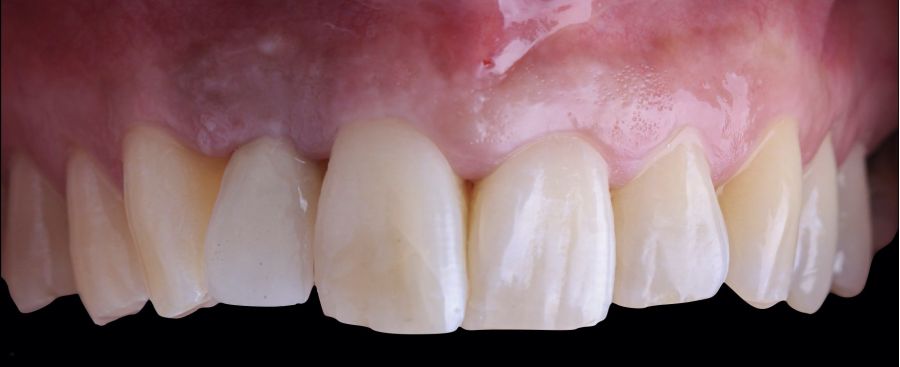

-Fase I: se realizó la extracción atraumática del resto radicular 1.2 y se efectuó un legrado del tejido de granulación. A continuación, se realizó el relleno del alveolo mediante un injerto óseo bovino inorgánico (0,25-1mm) combinado con fibrina autóloga rica en plaquetas y leucocitos. Finalmente, se suturó aproximando los bordes mediante 4 puntos simples desde el margen mucoso vestibular al palatino. Después, la paciente siguió usando su prótesis parcial removible como restauración provisional (Figura 1).

-Fase III: tres meses tras la colocación del implante, la situación del tejido blando era favorable (Figuras 5 y 6). Se tomó una impresión digital mediante escáner intraoral para la realización de un provisional atornillado de polimetilmetacrilato (PMMA). Respecto a la corona implantaria definitiva se realizó una restauración cemento-atornillada con una interfase de titanio nitrurado adaptando el diseño al perfil de emergencia ya consolidado con la prótesis provisional. La corona se realizó por CAD-CAM en zirconio con reducción completa y estratificación de cerámica feldespática de recubrimiento para zirconio (Figura 7).

El resultado clínico final fue satisfactorio cumpliendo las demandas estéticas del paciente. Los tejidos blandos estaban morfológicamente y dimensionalmente estables sin ningún signo de inflamación. Sin embargo, los cambios del tejido blando periimplantario (espesor volumétrico vestibular) fueron demostrados de manera cualitativa y cuantitativa (Figuras 8 y 9). En el postoperatorio inmediato (T1), la ganancia media obtenida al comparar T0 frente a T1 fue de 0,88 ± 0,15 mm con un incremento máximo de 1,1 mm. Al comparar T0–T2, se observó una ganancia media de 0,73 ± 0,23 mm. Es decir, se ha producido una contracción de volumen de 0,16 mm desde la colocación del injerto (T1) hasta pasado un mes y medio (T2).